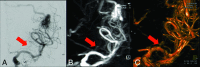

Background and purpose: 4D DSA allows acquisition of time-resolved 3D reconstructions of cerebral vessels by using C-arm conebeam CT systems. The aim of our study was to evaluate this new method by qualitative and quantitative means.

Materials and methods: 2D and 4D DSA datasets were acquired in patients presenting with AVMs, dural arteriovenous fistulas, and cerebral aneurysms. 4D DSA was compared with 2D DSA in a consensus reading of qualitative and quantitative parameters of AVMs (eg, location, feeder, associated aneurysms, nidus size, drainage, Martin-Spetzler Score), dural arteriovenous fistulas (eg, fistulous point, main feeder, diameter of the main feeder, drainage), and cerebral aneurysms (location, neck configuration, aneurysmal size). Identifiability of perforators and diameters of the injection vessel (ICA, vertebral artery) were analyzed in 2D and 4D DSA. Correlation coefficients and a paired t test were calculated for quantitative parameters. The effective patient dose of the 4D DSA protocol was evaluated with an anthropomorphic phantom.

Results: In 26 patients, datasets were acquired successfully (AVM = 10, cerebral aneurysm = 10, dural arteriovenous fistula = 6). Qualitative and quantitative evaluations of 4D DSA in AVMs (nidus size: r = 0.99, P = .001), dural arteriovenous fistulas (diameter of the main feeder: r = 0.954, P = .03), and cerebral aneurysms (aneurysmal size: r = 1, P = .001) revealed nearly complete accordance with 2D DSA. Perforators were comparably visualized with 4D DSA. Measurement of the diameter of the injection vessel in 4D DSA was equivalent to that in 2D DSA (P = .039). The effective patient dose of 4D DSA was 1.2 mSv.

Conclusions: 4D DSA is feasible for imaging of AVMs, dural arteriovenous fistulas, and cerebral aneurysms. 4D DSA offers reliable visualization of the cerebral vasculature and may improve the understanding and treatment of AVMs and dural arteriovenous fistulas. The number of 2D DSA acquisitions required for an examination may be reduced through 4D DSA.